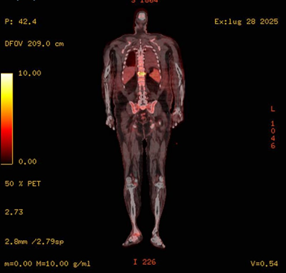

Given the presence of an intracardiac device and persistent MRSA bacteremia, both transthoracic and transesophageal echocardiography (TTE and TEE) were promptly performed. These showed no evidence of valvular vegetations or leadassociated infection. Nevertheless, the ongoing positivity of blood cultures raised concern for disseminated opportunistic infections. A contrast-enhanced full-body CT scan revealed multiple bilateral pulmonary nodules consistent with septic emboli (Figure 1), as well as a chronic right subdural hematoma and a hyperdense focus in the right frontal region. Whole-body 18F-FDG PET/CT (Figures 2,3) demonstrated no abnormal uptake at the pacemaker pocket or along the leads, but revealed increased metabolic activity in the D11 vertebral body (SUV max 12.9), and in the right talus, tarsal bones, and surrounding soft tissues of the lateral malleolus (SUV 7.8) findings suggestive of vertebral osteomyelitis (spondylodiscitis) and chronic osteomyelitis, respectively. Additionally, a reversed liver-to-spleen metabolic gradient (spleen SUV 5.4) was observed, likely reflecting reactive inflammatory changes.

Figure 3: Coronal fused 18F-FDG PET/CT image showing intense hypermetabolic activity at the D11 vertebral body (SUV max 12.9), consistent with spondylodiscitis. Notably, the spleen shows increased uptake relative to the liver (inverted liverspleen gradient), suggestive of reactive/inflammatory splenic hypermetabolism.